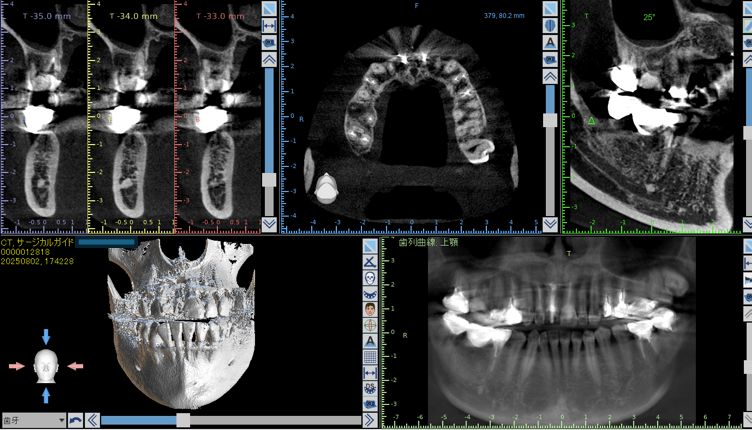

当院では、体の歪みを調べ、その方にとって無理のない安定した顎位を見つけ出し、その位置で噛み合わせを構築することを重要視した矯正治療を行っています。

また、歯列矯正だけではなく、全顎的に歯の治療(補綴治療)を必要とする方も体の歪みをみる上で治療をすることがとても重要です。